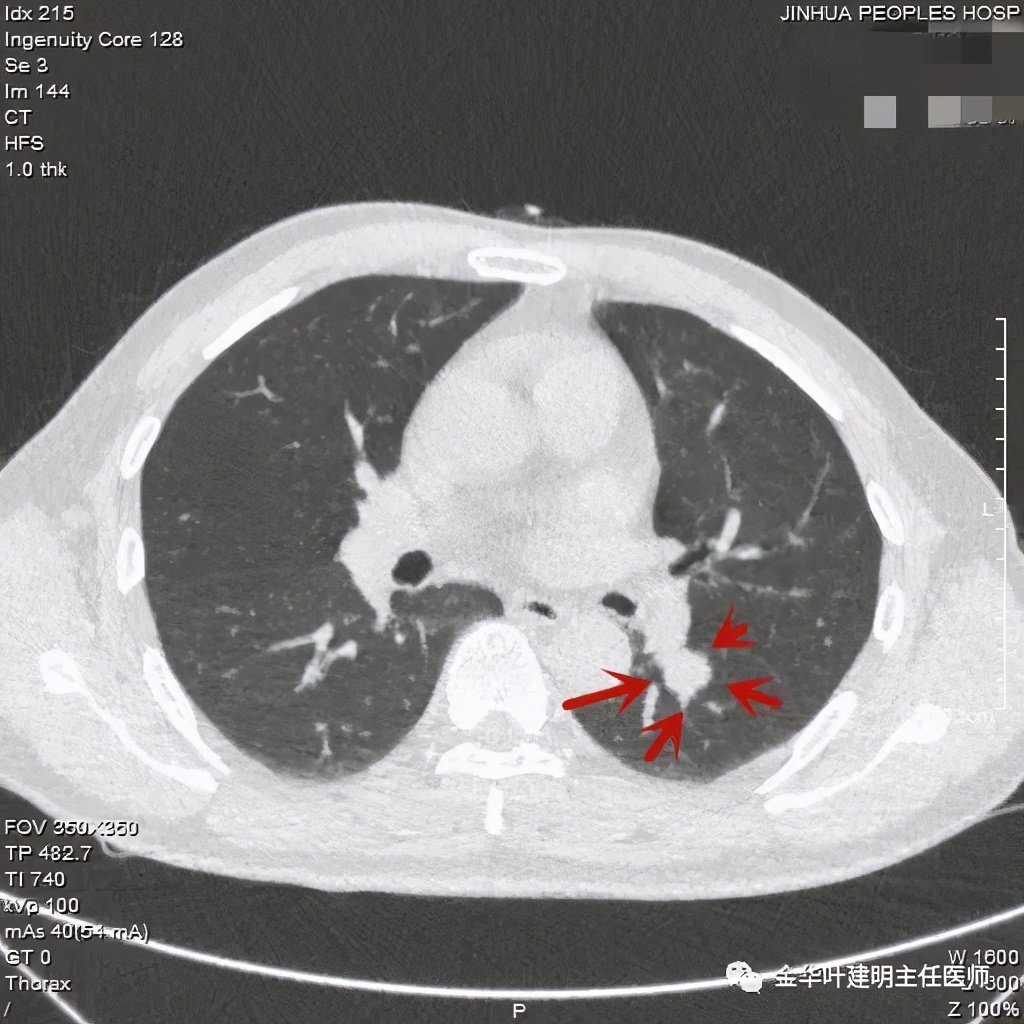

七、浸润性腺癌的其他型:

上图此例实性结节,是实体型,我们发现其影像特征: 病灶有浅分叶、细毛刺、支气管截断征、膨胀性,密度高而密 (比腺泡型实、比粘液癌高、比鳞癌或小细胞癌更具膨胀性)。

但是上面这几例,因为不管怎样的组合,都是实性密度+实性密度,这时仅从影像上就非常难以判断具体的亚型,不过,我们要根据相关的影像特征判断它为恶性,而且该尽早取得病理依据,能手术的要抓紧、不能手术的也要穿刺等得到病理类型的确诊后积极治疗,这就够了!